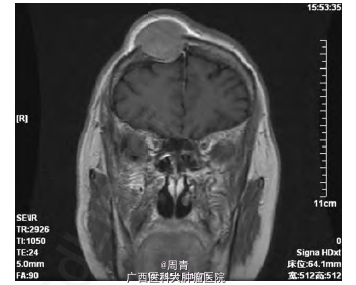

入院行体格检查发现: 右侧前额部包块,隆起明显,直径约5cm,形态规则,表面光滑,质软,边界清,无触痛,活动度差,周围可触及动脉搏动。患者未诉有任何疼痛、瘙痒等不适,追问病史,诉3 个月前偶然发现该肿物,生长缓慢。右侧前额部包块超声检查结果见: 皮下软组织内可探及范围约2.8cm×2.2cm×3.2cm的低回声包块,侵犯颅骨,形态尚规则,边界尚清,内回声尚均匀,可及动静脉血流信号,可引出动脉频谱,RI:0.90。考虑恶性肿瘤转移可能。头颅MRI 增强扫描,提示: 右额骨区可见35mm×35mm×37mm 大小占位病变,病变破坏颅骨内外板并膨胀性改变,增强扫描明显强化; 余颅内未见明确异常信号,脑室系统及脑沟、脑裂增宽; 中线结构无移位,符合恶性肿瘤改变( 图1) 。